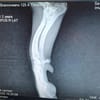

Licas ist ca. 11/24 geboren, etwa 30 cm groß und wiegt ungefähr 7 kg. Er wurde gemeinsam mit seiner Mama verlassen auf einem Feld in Rumänien gefunden. Eine Tierschützerin hat die zwei aufgenommen das war bereits im Oktober letzten Jahres. Doch Licas brachte ein schweres Schicksal mit: Sein Vorderbein ist gelähmt. Nach dem Röntgen stand fest eine Amputation oder eine Prothese könnten ihm helfen, schmerzfrei und unbeschwert durchs Leben zu gehen.